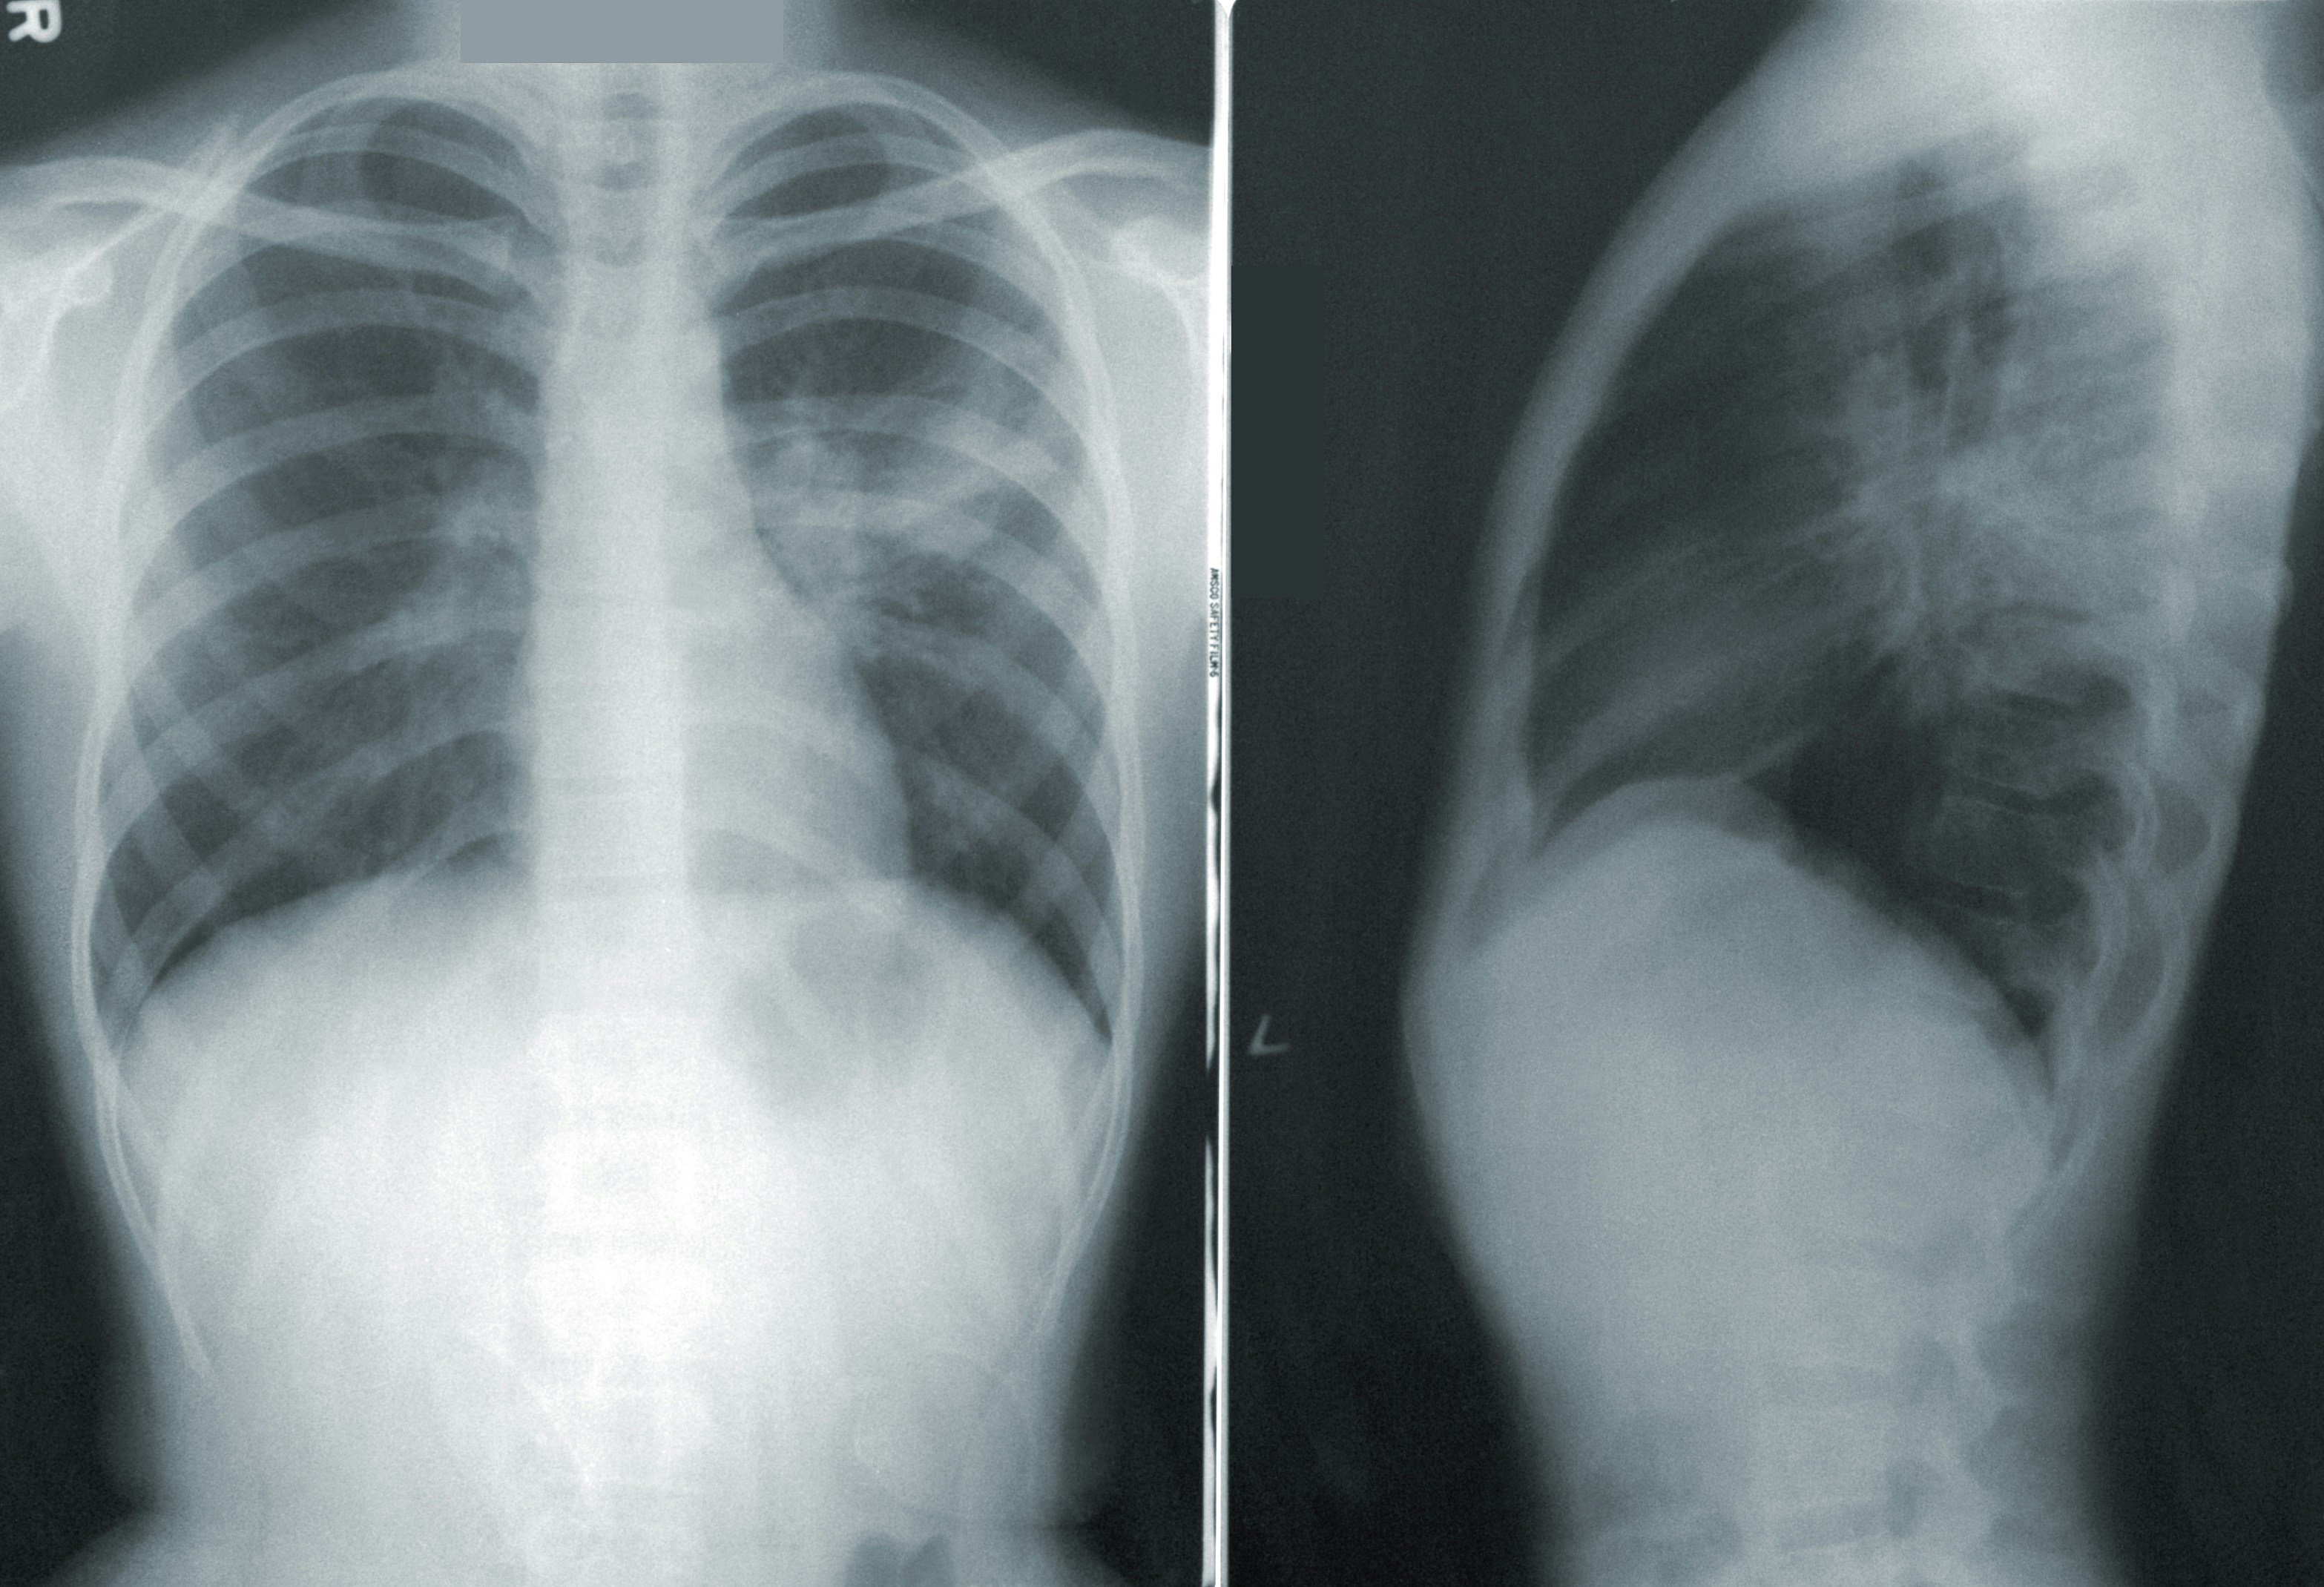

- 흉부 X선: 폐 염증 부위를 확인합니다.